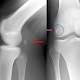

Die Ärztezeitung berichtete vor einiger Zeit über eine 26-jährige Patientin, die zehn Jahre mit einem 3,7 cm langen, abgebrochenen Zahnstocher im Fuß lebte. Röntgenbilder lieferten zuvor stets falsch negative Befunde.